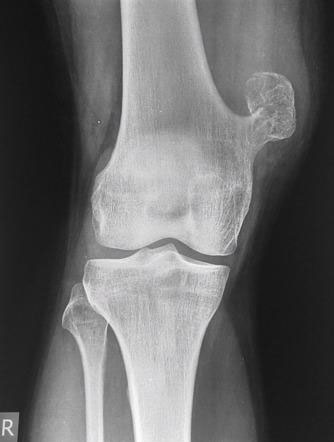

Опухоли костей являются редкими поражениями. Большая часть таких опухолей - доброкачественные образования, которые часто обнаруживаются случайно при радиологических исследованиях, проводимых по другим причинам. Что касается жалоб, они обычно проявляются отеком и болью. В редких случаях они обнаруживаются вследствие вызванного ими перелома в месте их расположения. Наиболее часто встречающимися доброкачественными образованиями являются остеоид-остеома, остеохондрома (экзостоз), энхондрома, неоссифицирующая фиброма, эозинофильная гранулема, простая костная киста, фиброзная дисплазия и внутрикостная липома / ганглия.